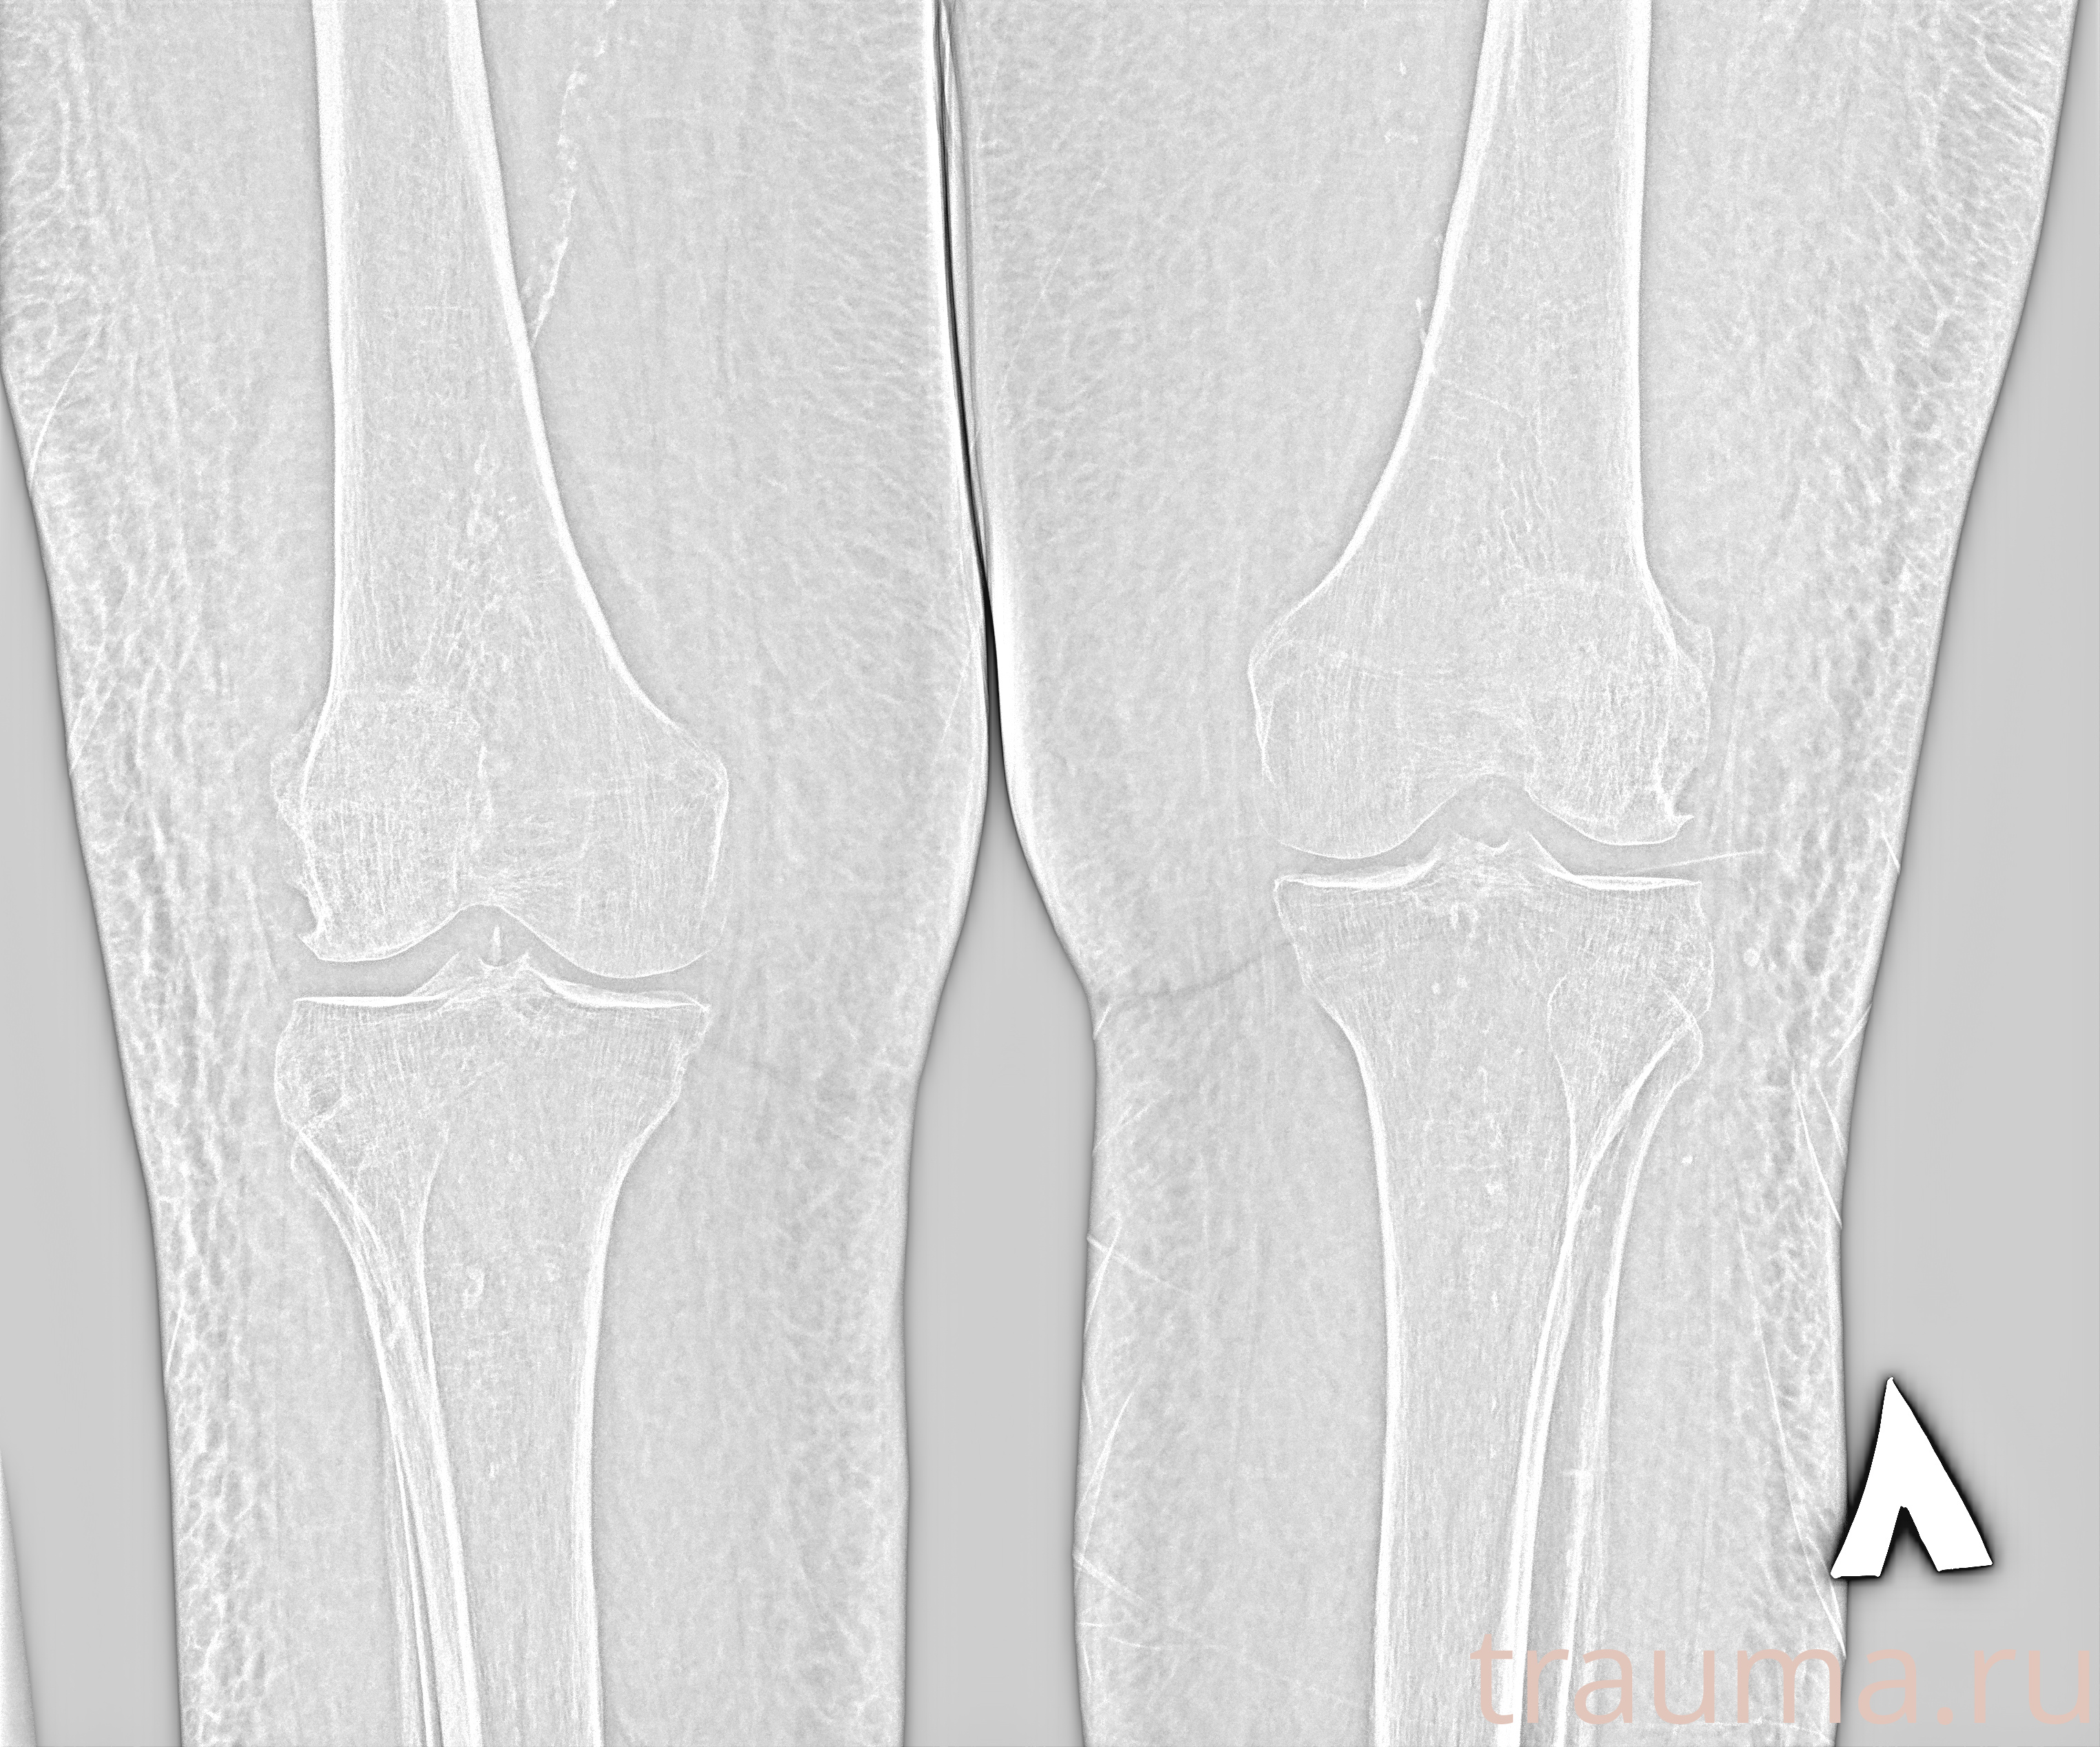

Рентгенограммы

Рентген на дому: по вашему адресу приезжает врач-рентгенолог, травматолог-ортопед с мобильным рентгеновским аппаратом, проводит диагностику травмы или заболевания, делает необходимые рентгенограммы, дает рекомендации по дальнейшему лечению. Получить качественные снимки в домашних условиях возможно благодаря уникальной методике, разработанной МосРентген Центром для института  Склифосовского